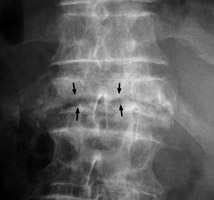

Diagnosis:Avascular Necrosis Discussion:Single frontal radiograph of the spine revealing a horizontally oriented linear area of lucency within the body of a single collapsed vertebral body. The intravertebral vacuum cleft sign is a gas-density cleft with a transverse separation of the vertebral body, appearing in extension and disappearing in flexion. It is secondary to local bony ischemic necrosis with nonhealing vertebral collapse. This ischemic vertebral fracture is not known to occur secondary to inflammation or neoplastic causes. References: